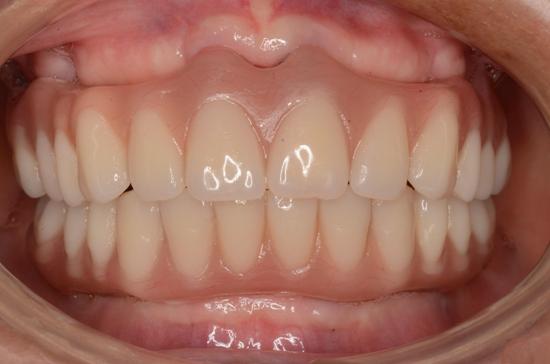

• 假牙製作階段

植體接出後,給予臨時假牙試戴,進行調整咬合與美觀部位的修飾,待病人適應一段時間後,依據調整好的咬合狀態進行印模製作永久假牙。(圖01-03)